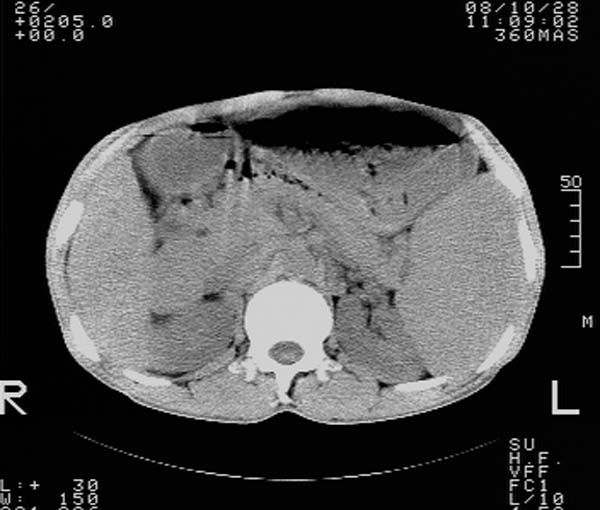

m,65y。半年前发现颈小结节,逐渐增多增大,现双侧耳后、颌下及颈部表浅淋巴肿大。胸片示双肺门增大。外院曾穿刺诊断为淋巴结核。在我科作胸腹部ct,我们觉得外院病检有误。现将图像上传请战友讨论。

纵隔内及腹膜后广泛淋巴结肿大,脾大,肝内似可见低密度影,结合病史半年前发现颈小结节,逐渐增多增大,现双侧耳后、颌下及颈部表浅淋巴肿大。考虑淋巴瘤。

我们也是首先考虑淋巴瘤。只是外院病检报告是结核。让人迷惑。肝左叶多发低密度占位,没增强不好定论。

纵隔,双肺门腹膜后多发淋巴结重大,非融合,肝脾轻度肿大,双肺野弥漫性小结节;考虑淋巴瘤,结节病可能性

纵隔内,双肺门、腋窝及腹膜后多发肿大淋巴结影,肺内小结节影,肝脾体积增大,支持淋巴瘤。肝内多发低密度影,考虑小囊肿。

纵隔内,双肺门、腹膜后多发肿大淋巴结影及颈部淋巴结肿大,肝脾体积大.结合临床,淋巴瘤可能性大。